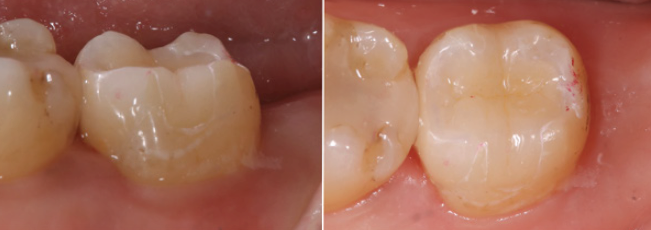

後方臼歯の力のコントロールが困難であるため、極力現状を維持できるような治療計画を立案した。防湿下で齲蝕検知液が染まる歯質を完全に除去する。露髄した状態をマイクロスコープ下で確認し歯髄の表面に毛細血管が存在し、血流があるか確認し、歯髄が壊死していないことを確認。次亜塩素酸ナトリウムを浸した綿球を露髄面に置き、2分間で止血、消毒を行う。完全止血を確認後、MTAセメントをペースト状にして充填。その上をCRで履層(図6)。修復は極力エナメル質の硬度に近似した材質を選択し、保存療法を行なった(図7)。

術後7年経過、露髄した髄角部には、デンティンブリッジが形成されMTAセメントと歯髄の間に硬組織が認められる(図8)術直後と7年後の比較)。口腔内の状態は多少の咬耗は認めるが、ナイトガードを使用することでパラファンクションに対応しながらメンテナンス継続中。

(図7)二ケイ酸リチウムガラスセラミックにて修復